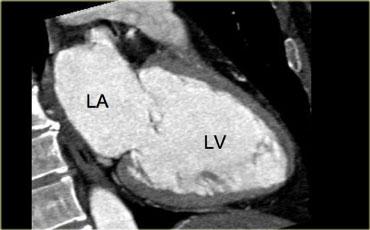

Mặt cắt 2 buồng

Mặt cắt 2 buồng trong hình bên trái đạt được bằng cách xoay hình ảnh vuông góc với van hai lá và song song với vách liên thất.

Trục này cho cái nhìn tổng quan về nhĩ trái, thất trái và van hai lá.

Đây là mặt cắt tốt để phân tích chức năng thất, đặc biệt là thành dưới và thành trước.